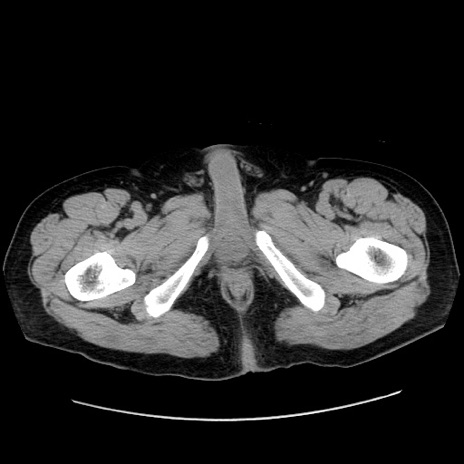

症例30(横断像)

【症例】80歳代男性

【主訴】臍周囲痛

【現病歴】約6時間前から臍下部痛が出現。次第に腹部膨隆・背部痛も生じてきたため来院。背部痛の場所は変化しない。

【身体所見】意識清明、BT 36.3℃、BP  131/87mmHg、P 87bpm、SpO2 100%(RA)、臍周囲自発痛・圧痛あり、反跳痛なし、自発痛部位に一致して板状硬あり、腹部膨隆、腸雑音減弱、CVA tenderness両側陰性。